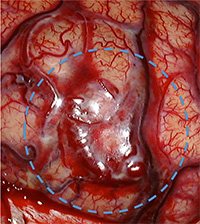

脳動静脈奇形に関与する動脈、静脈、奇形部分本体を周囲の脳組織から剥離して、摘出します。脳動静脈奇形の大きさ、場所によって手術の難しさは異なりますが、正常な血管と、異常な血管を見分けながら、奇形部分のみを取り出す必要があり、脳神経外科手術の中でも難しく、そして時間のかかる手術の一つです。

手術中の血管奇形部分の写真。青丸部分に拡張した血管網が見られます。(下図)